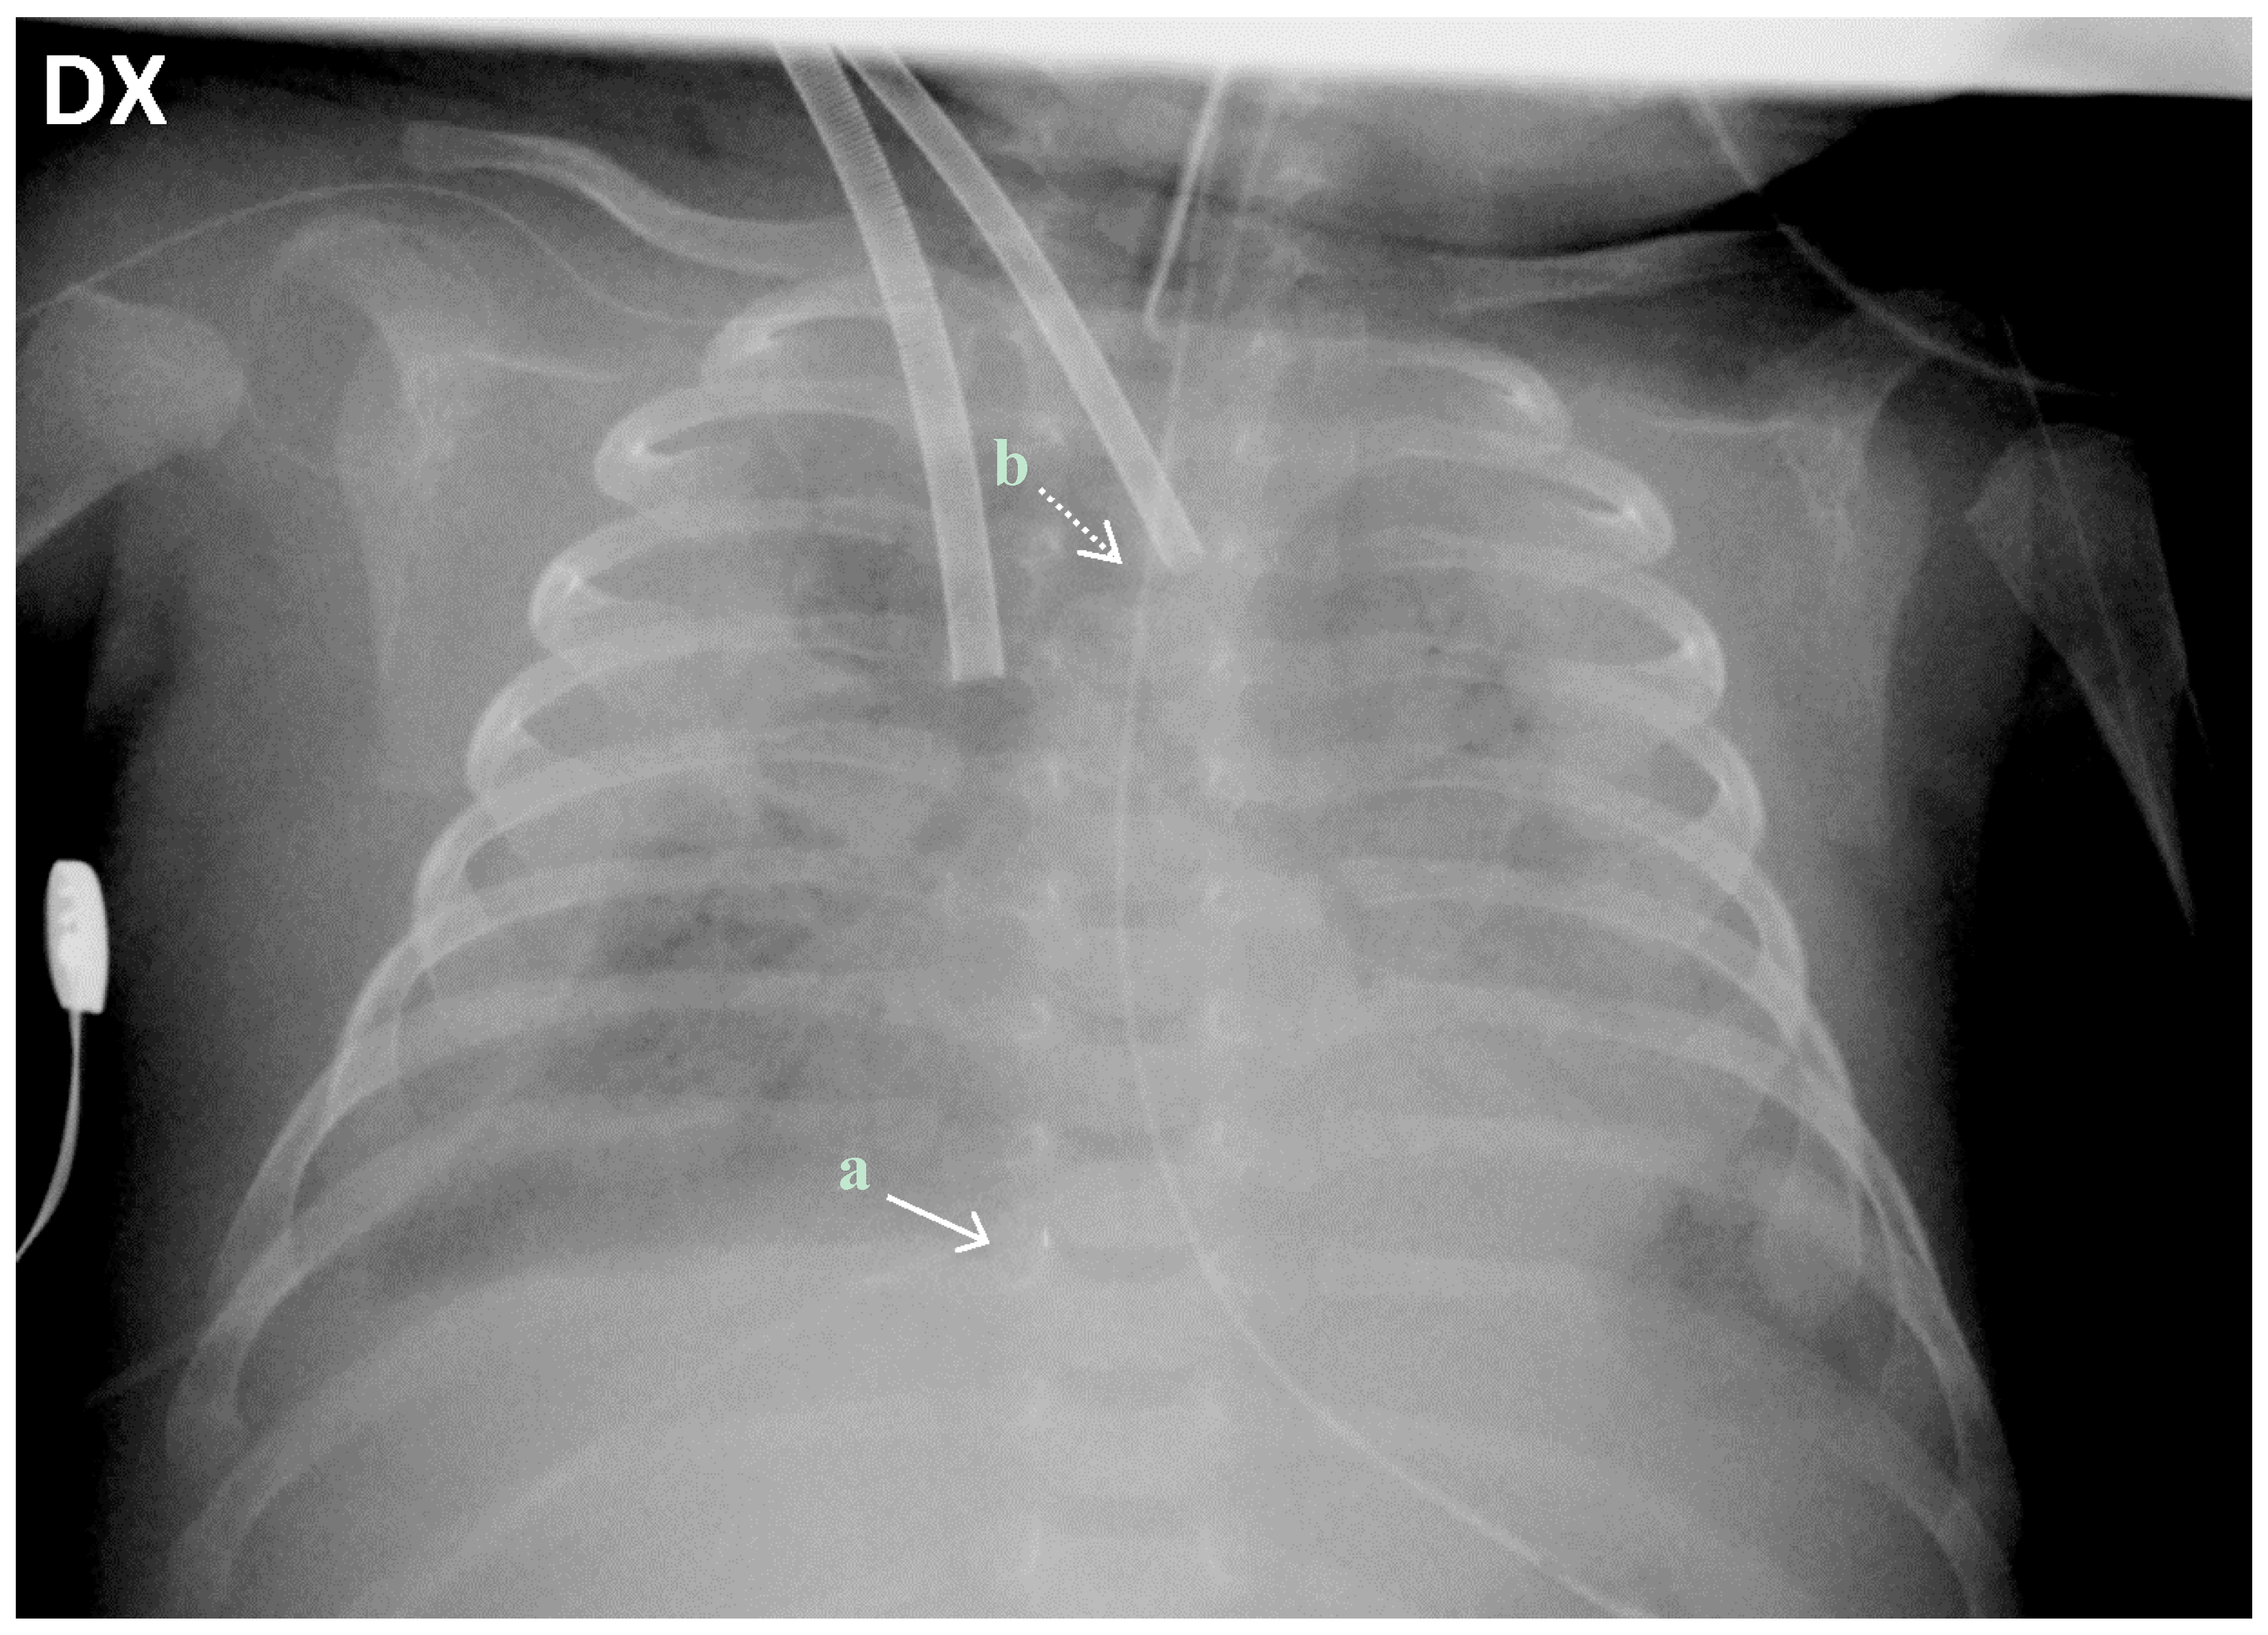

The patient weighed 3300 g at the beginning of the procedure. Surgical open cannulation was performed via the neck vessels, through a surgical exploration and dissection of the vessels (Figure 1). Correct cannula position was confirmed by chest X-ray (Figure 2) and trans-thoracic echo. Cardiopulmonary bypass (Quadrox iD, Maquet Getinge®) was established from the right internal jugular vein (10 Fr Medtronic®) to the right carotid artery (8 Fr Medtronic®), maintaining a blood flow of 350–500 mL/min (Cardiac Index 120–150 mL/kg/min).

Figure 2.

Chest X-ray of the patient 48 h after the start of ECLS support. Correct positioning of the (a) distal tip of the drainage cannula in the junction between the superior vena cava and the right atrium (straight white arrow) and (b) distal tip of the inflow cannula in the junction between the right common carotid artery and the aortic arch (dotted white arrow).